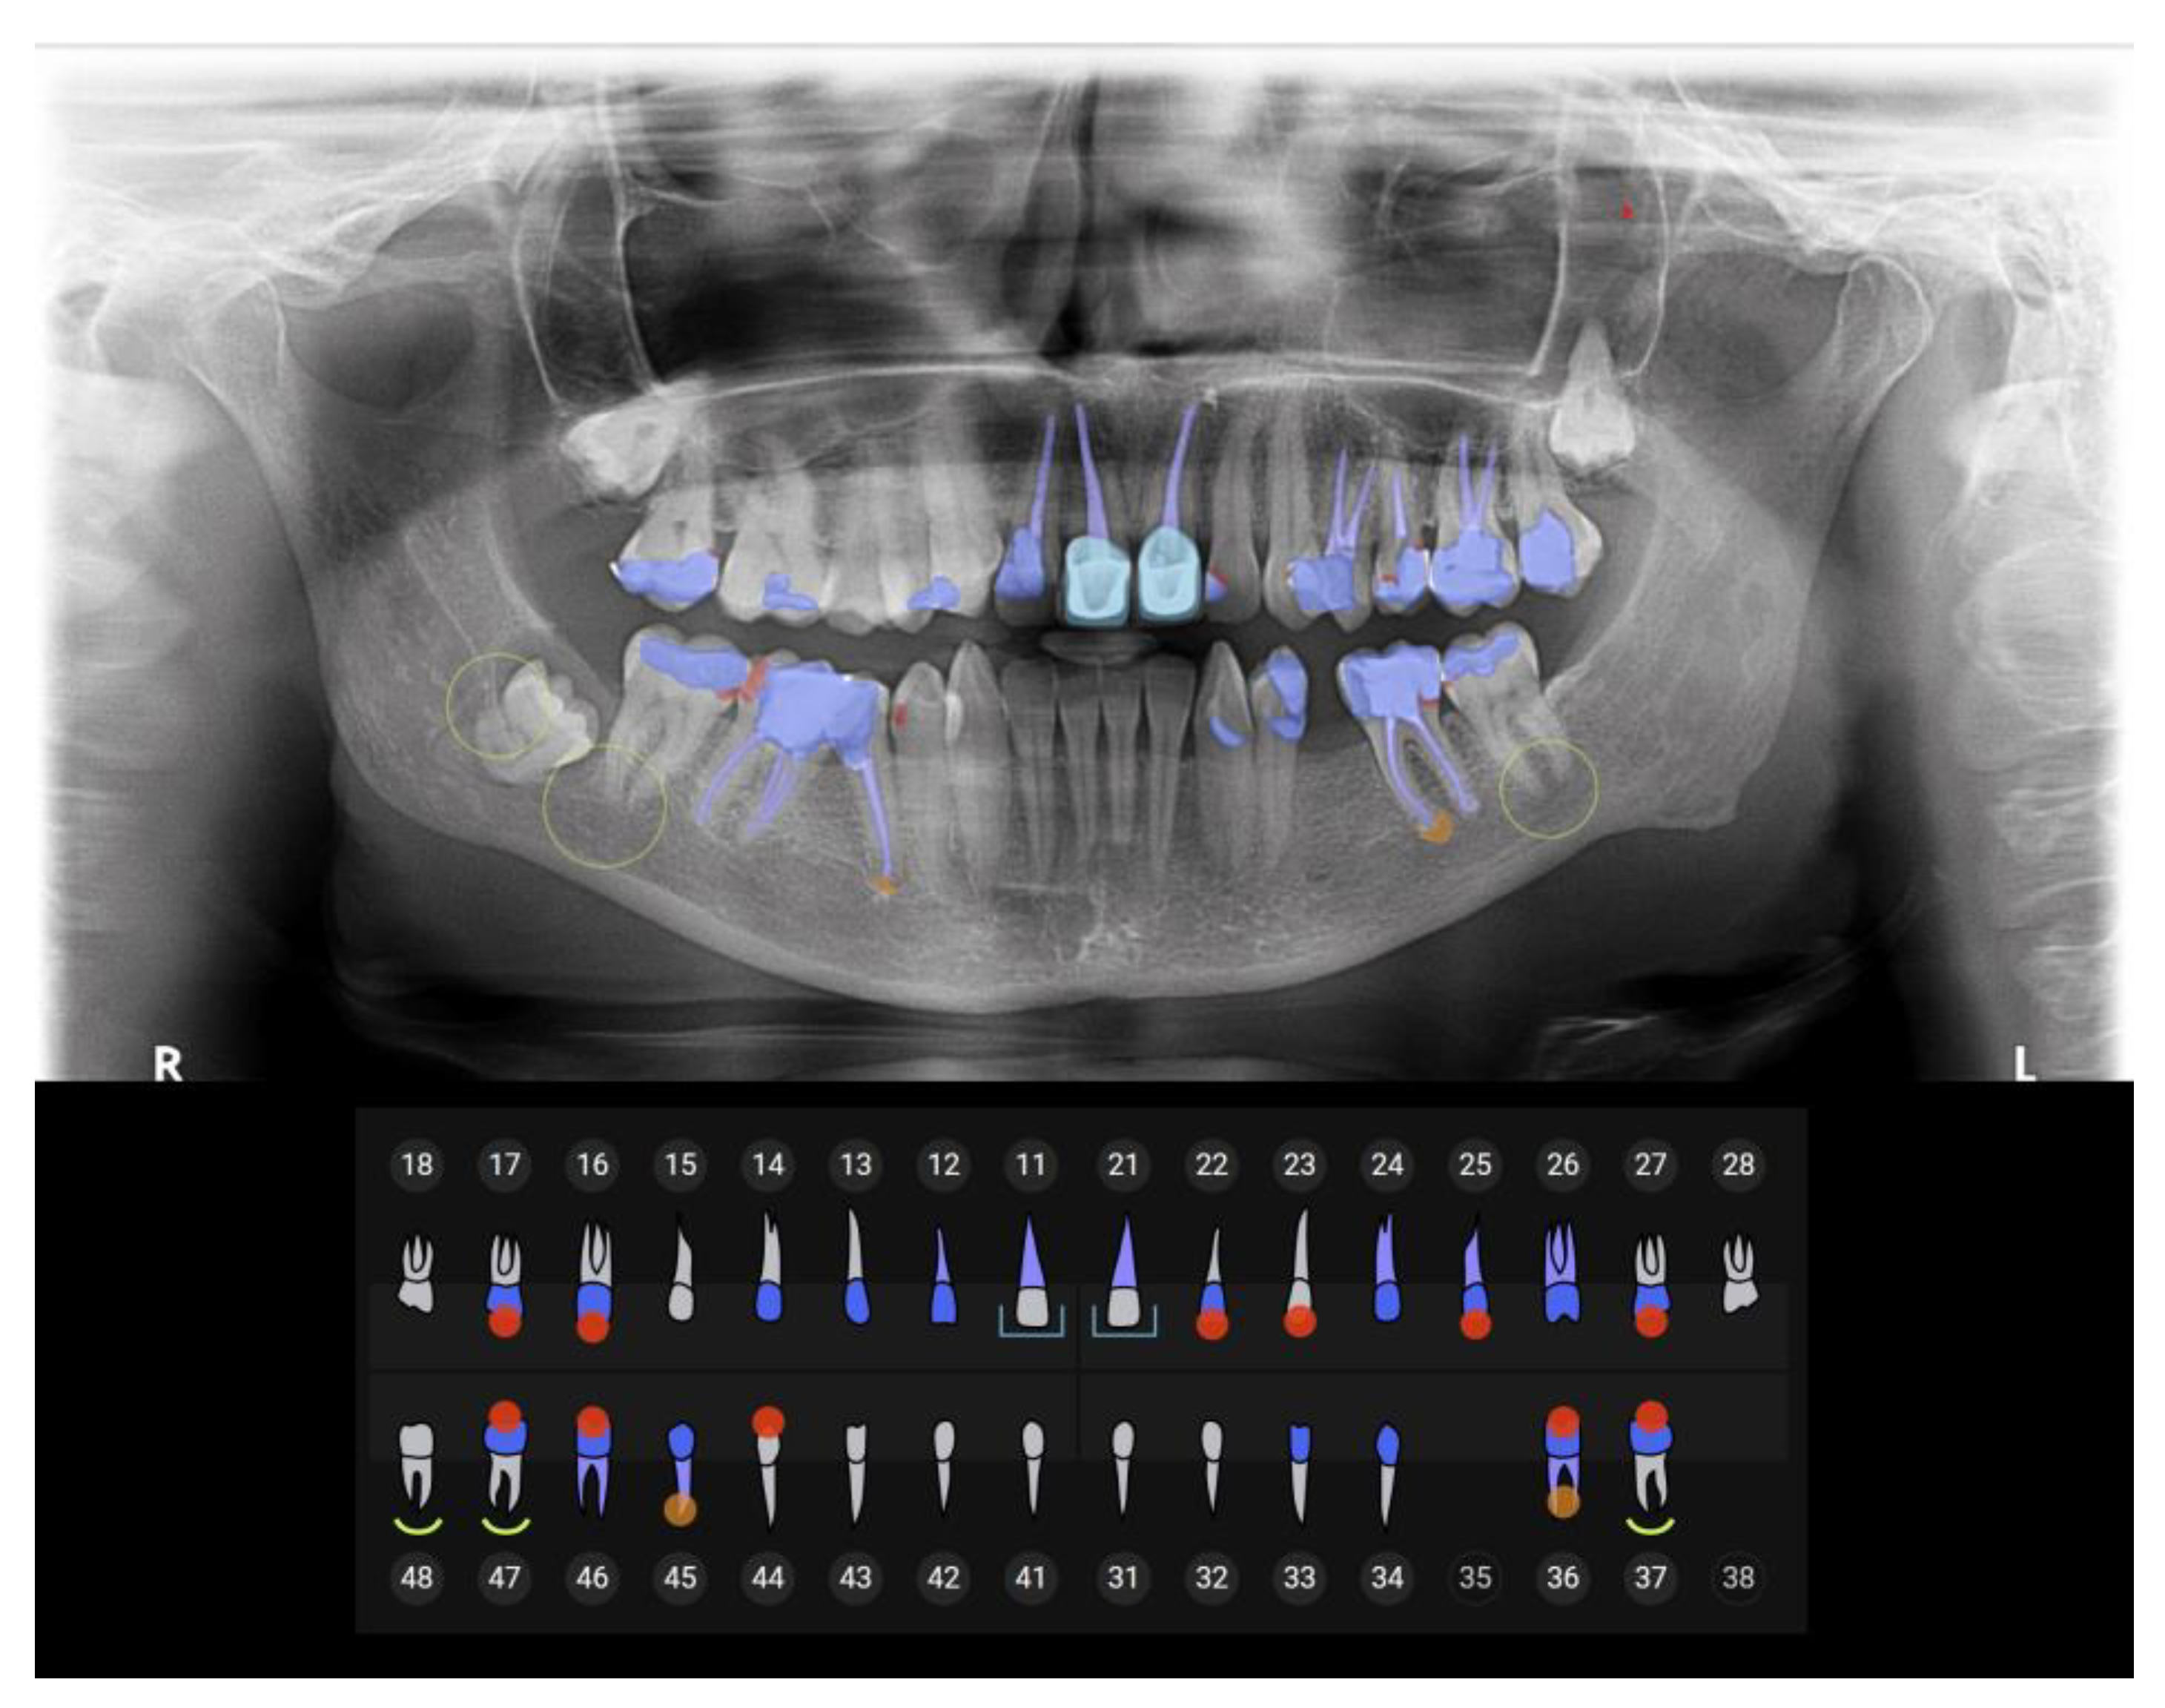

4.1. AI Software